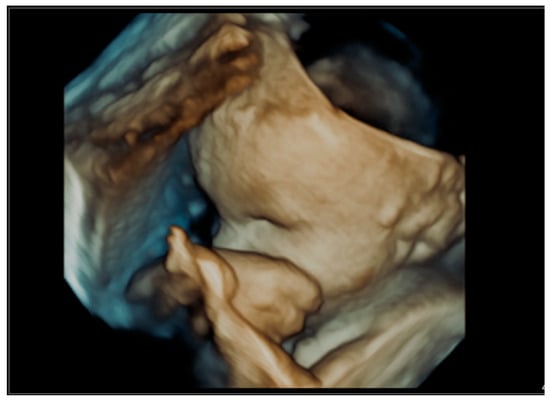

An image of a fetal ear in 2D ultrasound examination. Measurement of the fetal ear at the gestational age of 35 weeks and 1 day.

Figure 9.

An image of a fetal ear auricle in 3D ultrasound examination at the gestational age of 35 weeks and 1 day. A genetic test of the amniotic fluid: the use of whole genome oligonucleotide microarrays (CytoSure Constitutional v3 (8x60k), Oxford Gene Technology, GRCh37/hg19) with an average resolution of 120 kpz–arr(X,Y)x1,(1-22)x2–No abnormalities were detected.

Figure 10.